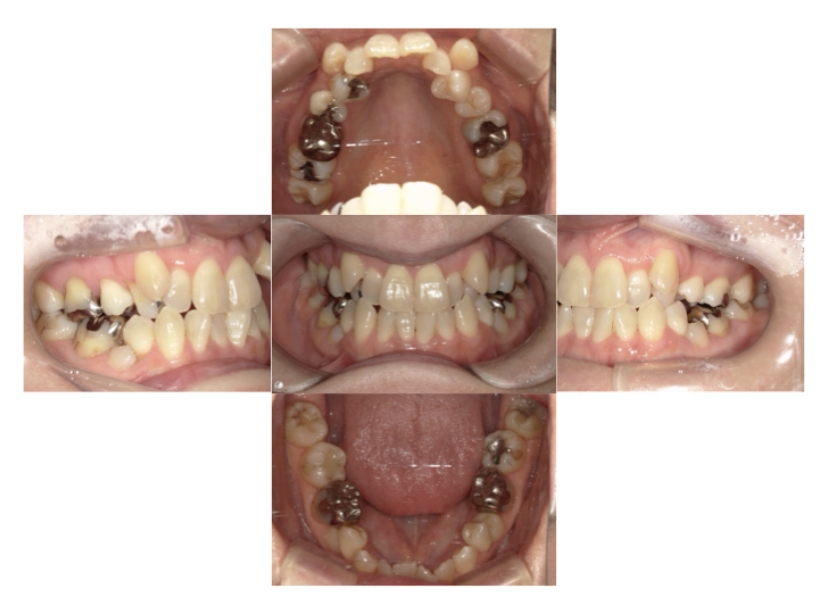

BEFORE

AFTER

症例4

下顎前突、叢生

抜歯

ブラケット矯正

症例解説

上下顎叢生、反対咬合(上下の前歯のガタガタ、若干受け口)のケースです。

装置はラビアル(上下表側)で、上下顎の小臼歯を4本抜歯を行っています。抜歯したスペースを使って、上下の叢生改善と前歯の受け口の改善を行っています。

主訴 前歯のガタガタを治したい。

年齢・性別 45歳 女性

お住まいの地域 神奈川県川崎市

治療方針 抜歯スペースを利用して上前歯の叢生(ガタガタ)の改善と受け口の改善

抜歯部位 上顎左右第一小臼歯、下顎左右第二小臼歯

使用装置 ラビアル(上下表側)、顎間ゴム

治療期間 2年6か月

治療回数 20回

リテーナー クリアリテーナー